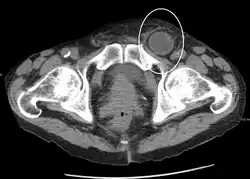

No diagnóstico de hérnias abdominais, a imagem é o principal meio de detectar hérnias diafragmáticas internas e outras hérnias não palpáveis ou não suspeitas. A tomografia computadorizada com múltiplos detectores (TCMD) pode mostrar com precisão o local anatômico do saco de hérnia, o conteúdo do saco e quaisquer complicações. A TCMD também oferece detalhes claros da parede abdominal, permitindo que as hérnias sejam identificadas com precisão.[9]